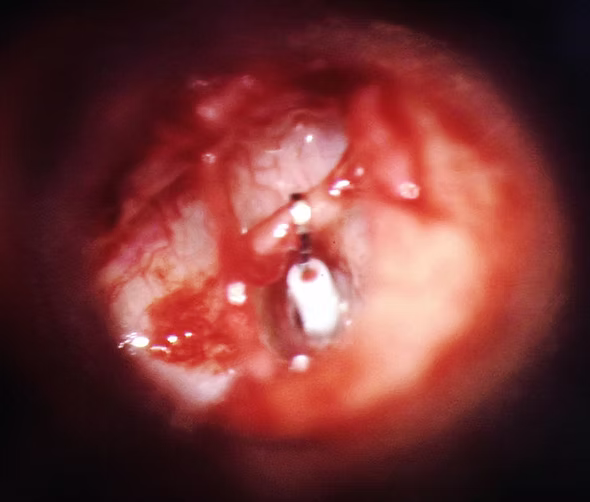

Prótesis de estapedotomía

Perforación de la platina y colocación de prótesis desde la ventana oval a la rama larga del yunque recuperando la transmisión de la onda sonora y mejorando la audición.